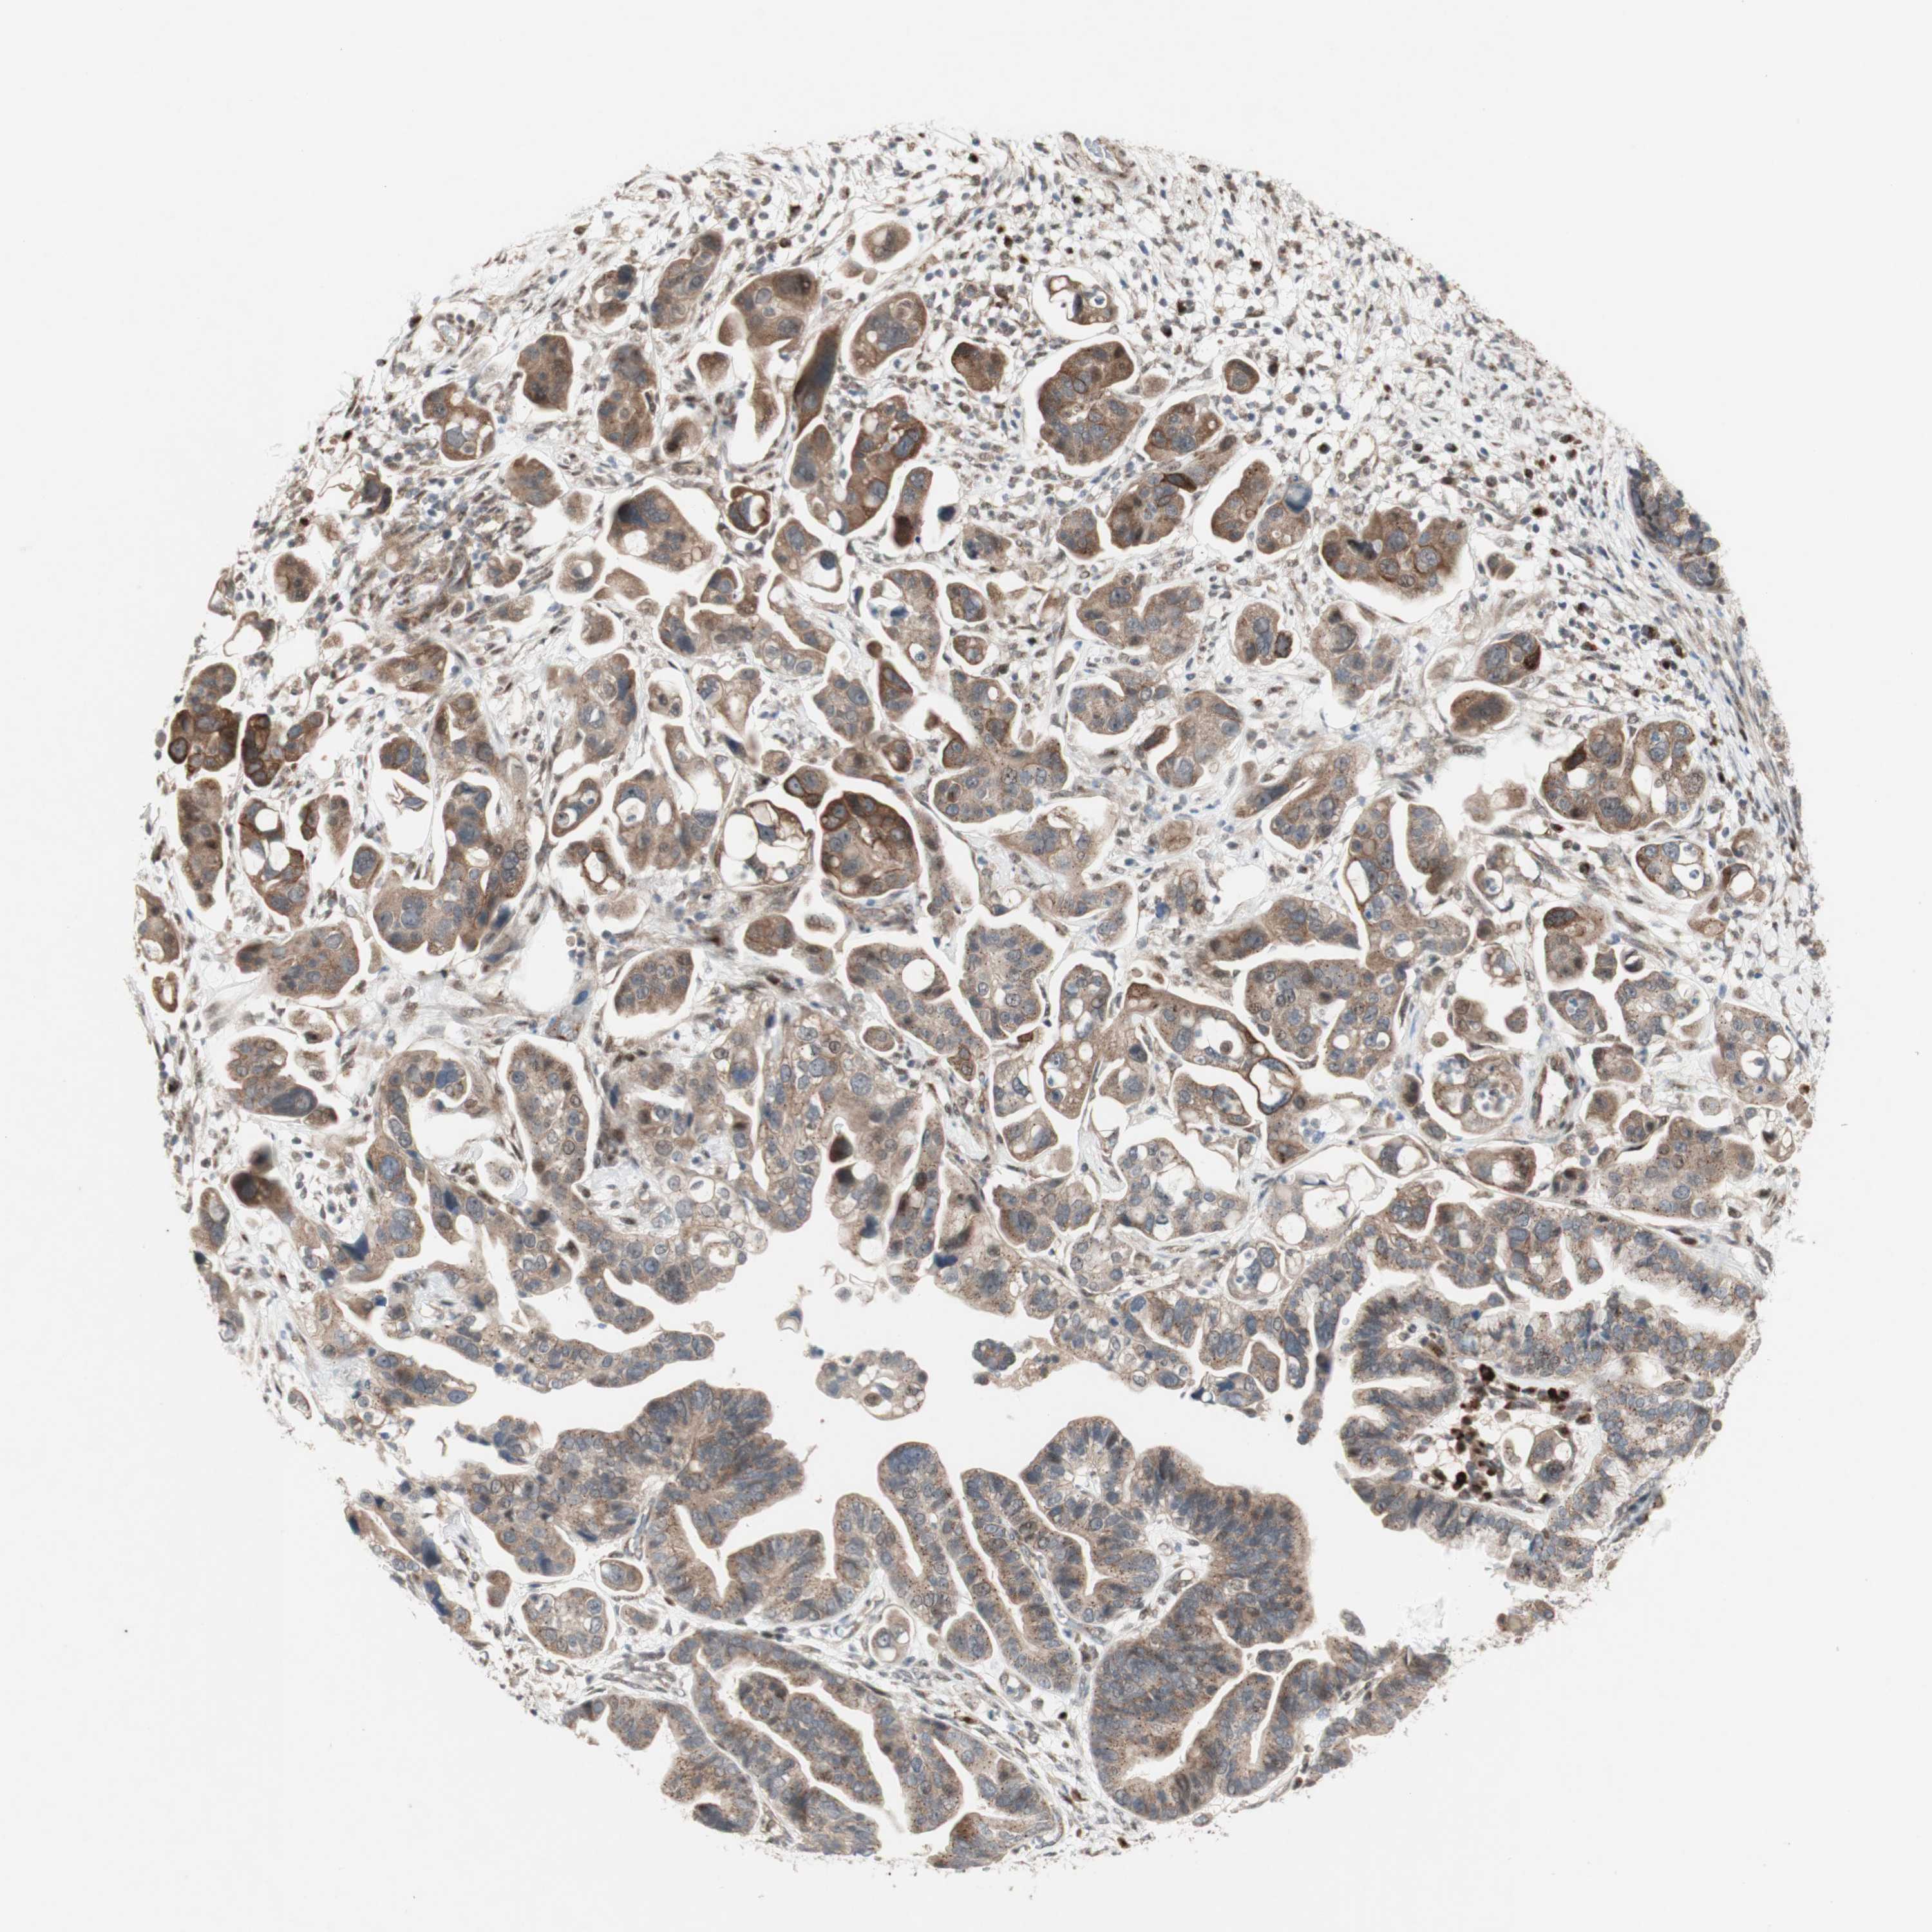

OVARIAN CANCER - Protein expressioni

A mouse-over function shows sample information and annotation data. Click on an image to view it in a full screen mode. Samples can be filtered based on level of antibody staining by selecting one or several of the following categories: high, medium, low and not detected. The assay and annotation is described here.

Note that samples used for immunohistochemistry by the Human Protein Atlas do not correspond to samples in the TCGA dataset.

Antibody stainingi

Antibody staining in the annotated cell types in the current human tissue is reported as not detected, low, medium, or high, based on conventional immunohistochemistry profiling in selected tissues. This score is based on the combination of the staining intensity and fraction of stained cells.

Each image is clickable and will lead to virtual microscopy that enables deeper exploration of all samples and also displays staining intensity scores, fraction scores and subcellular localization as well as patient and tissue information for each sample.

Antibody HPA077163

Antibody CAB011713

Cystadenocarcinoma, serous, NOS

Cystadenocarcinoma, mucinous, NOS

Carcinoma, endometroid

Carcinoma, NOS